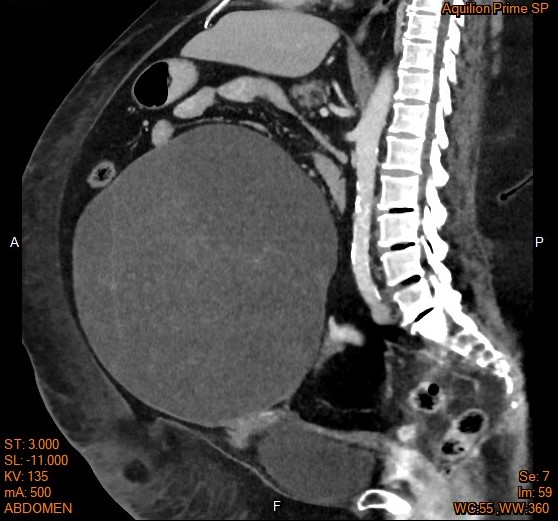

▎案例分享

58歲女性近三個月出現腹脹和體重增加,一開始患者症狀並未引起當時的高度警覺,經婦產科醫師檢查懷疑卵巢腫瘤,並進行腹部電腦斷層(CT)檢查(如圖片),結果發現約30公分的卵巢腫瘤。隨後,醫生決定安排手術治療。